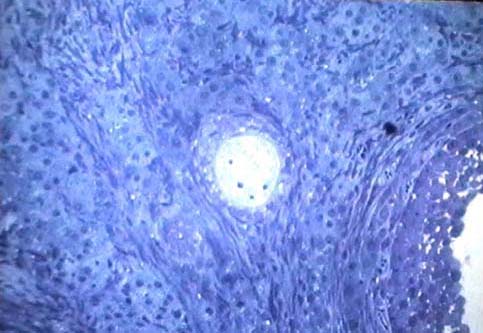

Niere und ableitende

Harnwege

Weiblicher Genitaltrakt